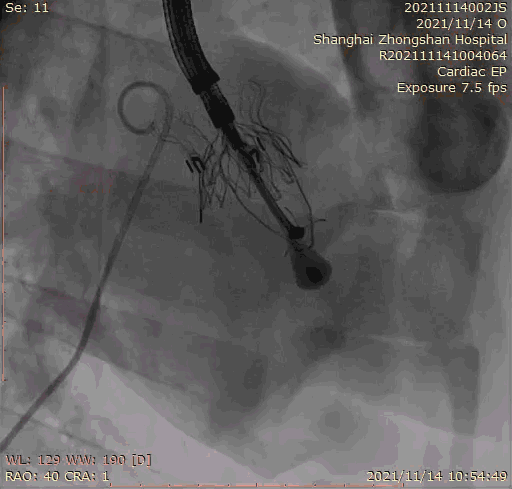

2021年11月14日星期日,復旦大學附屬中山醫(yī)院(以下簡稱中山醫(yī)院)葛均波院士團隊成功應用經(jīng)血管介入三尖瓣置換產(chǎn)品Lux-Valve Plus完成臨床前研究,并獲得圓滿成功!此次研究的成功預示經(jīng)血管三尖瓣產(chǎn)品Lux-Valve Plus已完成臨床前準備,即將開啟后期的正式臨床研究!

上海中山醫(yī)院葛均波院士、錢菊英院長、周達新教授、潘文志教授、潘翠珍教授、李偉教授共同完成此次臨床前研究。術(shù)后葛均波院士對Lux-Valve Plus的器械操作性能給予了高度評價,DSA和超聲影像也顯示出在本次研究中Lux-Valve Plus的安全性和有效性俱佳。

本次臨床前研究經(jīng)右側(cè)頸靜脈置入LuX-Valve Plus輸送系統(tǒng)可調(diào)彎鞘管,在DSA及超聲引導下將人工三尖瓣瓣膜植入到原有三尖瓣位置,利用獨特的錨定技術(shù)將人工瓣膜支架可靠固定在預定的位置。